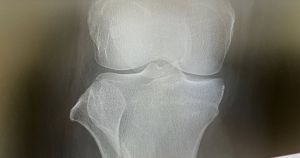

私個人としては、やはり5月ごろから痛みを覚え始めた膝の問題が、ずっと心身に重くのしかかっています。私が今年の漢字を選ぶとしたら「膝」で間違いないでしょう。

記者としての仕事やアルバイトにも支障が出て、今では痛くない時にどう歩いていたのかを思い出すのも難しいぐらい、痛みがあるのが当たり前の生活になりました。

公私混同記事として、変形性膝関節症の専門家に取材して、聞きたいことを根掘り葉掘り聞きもしました。

痛みも怖いですけれども、痛みで諦めることが増え、自分を卑下したり、自分がダメになったと、自分自身に負のレッテルを貼ってしまうことがとてもつらいことです。

それを励まし、痛みを取ろうとしてくれる主治医の言葉に救われた経験も書きました。